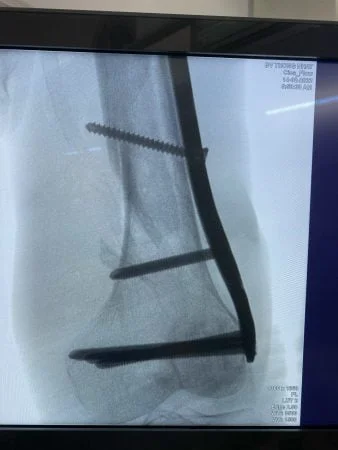

Phẫu thuật kết hợp xương ít xâm lấn (MIPO) trong điều trị gãy xương là phương pháp tiên tiến được ứng dụng phổ biến trên thế giới cũng như ở một số bệnh viện hàng đầu trong nước nhờ những ưu điểm vượt trội: cuộc mổ nhẹ nhàng, an toàn, ít tàn phá mô mềm, hạn chế nguy cơ nhiễm trùng, thời gian hồi phục nhanh. Đặc biệt là khả năng xử lý các triệt để tổn thương tương đương với mổ mở truyền thống, tính thẩm mỹ cao.

Hiện tại khoa ngoại CTCH Bệnh viện Thống Nhất đã và đang áp dụng phương pháp này thường xuyên, tuy nhiên tùy vào từng trường hợp và mức độ tổn thương mà bác sĩ sẽ tư vấn và đưa ra phươmg pháp điều trị hợp lý nhất.